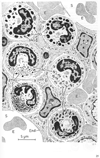

骨髄【こつずい】(骨髄は骨の内部、すなわち長骨の髄腔や骨端およびその他の骨の海綿骨の小柱骨の間を満たす組織で、血球を産生する造血組織である。発育期にある幼小児の骨髄はすべて赤色骨髄で占められているが、成長ともに長骨の骨髄には黄色骨髄が次第に増加する。7歳以後、黄色骨髄は上肢の長骨の遠位側から近位側に向かって次第に増加し、成人では、赤色骨髄は主として体幹の骨(頭蓋骨・椎骨・胸骨・肋骨)および上肢帯・下肢帯の骨(寛骨など)と上肢・下肢では上腕骨・大腿骨の海綿質の近位端に限られる。骨髄は骨髄腔および海綿質を満たす軟らかい組織で血球をつくる大切な場所である。胎生期や乳児期にはほとんどすべてが赤色骨髄であるが、成長とともに黄色骨髄におきかわり、成人では半量に達する。赤色骨髄は造血(血球新生)が行われる場所であるが、黄色骨髄は赤色骨髄が脂肪化して造血能力を失ったものである。さらに年をとると、黄色骨髄の脂肪組織は変性、萎縮し、骨髄はゼラチン様になる。これを膠様骨髄という。また、結合組織繊維におきかわったものを線維骨髄という。骨の栄養孔から入った動脈は何回も枝分かれし赤色骨髄のなかで洞様毛細血管(sinusoid capillary)となる。この血管は内腔が広いこと、内皮を血球が通りぬけること、内皮細胞に食作用の能力(phagocytic activity)があることを特徴とする。洞様毛細血管の外は造血組織になっており、ここでつくられた血球のうち、完成した血球だけが内皮をくぐりぬけ血管内にでるが、そのメカニズムはよくわかっていない。洞様毛細血管は集まって中心静脈となり栄養孔から外へ出る。造血組織は細網細胞と細網線維の網からなる細網組織であり、その網眼を数多くの種々の段階の造血細胞が満たしているのである。骨髄とは血液疾患の診断に際してきわめて大切で、骨髄穿刺によって骨髄をとりだして観察することが行われている。胸骨穿刺が最もよく用いられる。骨髄は骨の本質的構成要素ではない。骨髄のない骨は小型動物(ことに魚類)には至る所にみられ、造血は脾臓や肝臓で行われる。また人体でも、耳小骨のような小骨や鼻腔壁の薄い骨片は骨髄を欠いている。大きな骨でも、頭蓋骨では骨髄の代わりに空気をいれているものがある(含気骨)。これは骨格を軽くするためと考えられ、鳥類では体幹にも含気骨がよく発達している。赤色骨髄は造血組織が仮に骨の中の空間を利用して占拠しているのに過ぎないのである。)